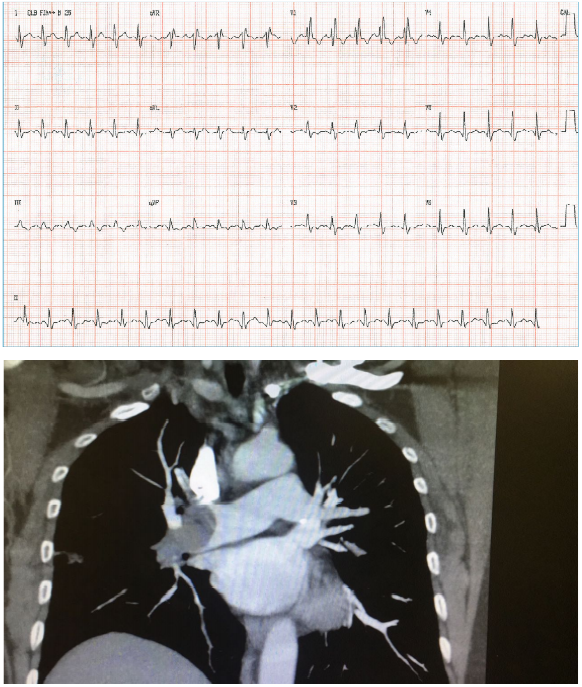

Sr. JG, 60 anos, procura o serviço hospitalar com falta de ar e dor torácica iniciada há 40 minutos. Referiu que, na

véspera, começou a se sentir mal e esteve no mesmo hospital, quando foi examinado e realizou radiografia de tórax

e eletrocardiograma. Na ocasião, os médicos lhe disseram que não encontraram anormalidades relevantes e deram

alta a ele, que foi para casa. O paciente possui histórico de tabagismo crônico. Exame físico: FC = 134 bpm, FR+

36irpm, PA = 89x58 mmHg, Oximetria = 85%, sudorético. AR = murmúrio vesicular fisiológico, sem ruídos

adventícios; ACV: bulhas rítmicas e fonéticas. Seguem abaixo as imagens do ECG e TC de tórax.

Qual a conduta CORRETA para esse paciente?